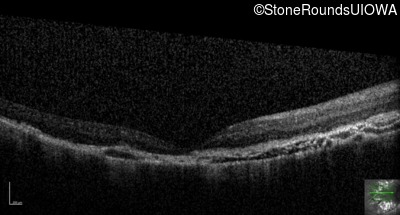

Optical Coherence Tomography - Right - 20/200 -1

Exemplar / OCT Stack